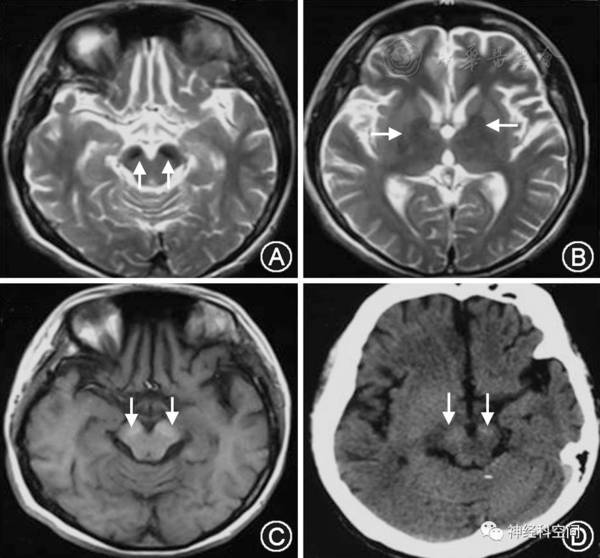

中枢神经系统表面铁沉积症一例并文献复习

言语困难,表述不清,确诊:中枢神经系统表面铁质沉积症,伴轻度小脑萎缩

中枢神经系统表面铁沉积症